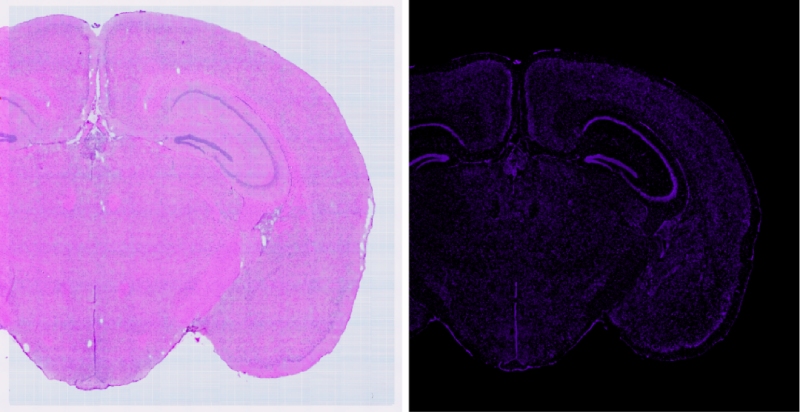

通過(guò)BH1000快速(20X,8mm*8mm,小于50S)得到高清明場(chǎng)圖像與高清的熒光(支持7個(gè)熒光通道,各通道有獨(dú)立傳感器,電動(dòng)切換,標(biāo)配明場(chǎng)、?DAPI、FITC和CY3)成像結(jié)果來(lái)選擇最優(yōu)的透化時(shí)間(需要選擇熒光最亮且符合相應(yīng)明場(chǎng)結(jié)構(gòu)無(wú)明顯逸散的梯度)

可以利用BH1000對(duì)明場(chǎng)及熒光掃描過(guò)程中經(jīng)常出現(xiàn)的拼接錯(cuò)誤進(jìn)行校準(zhǔn)(自主研發(fā)BMCHiper軟件,搭配自研半透半返模塊,實(shí)現(xiàn)圖像無(wú)錯(cuò)校準(zhǔn)),得到原片無(wú)錯(cuò)高清的熒光圖像與原片無(wú)錯(cuò)高清的明場(chǎng)圖像,為后續(xù)空間數(shù)據(jù)準(zhǔn)確的定位和可視化提供基礎(chǔ),使得復(fù)雜的轉(zhuǎn)錄組數(shù)據(jù)能夠轉(zhuǎn)化為最直觀,最精準(zhǔn)的生物學(xué)見(jiàn)解。